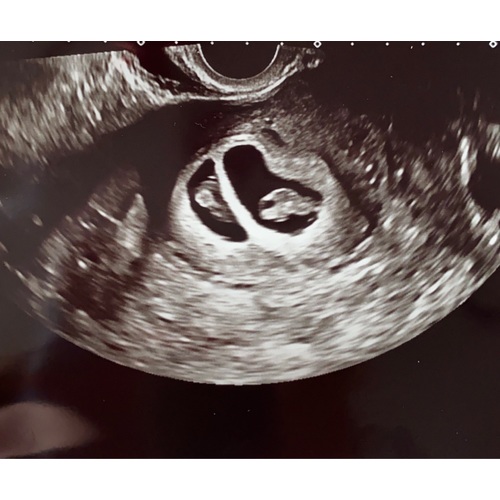

Wij zijn voor de eerste keer in verwachting 鈾ワ笍 na jarenlang proberen en vruchtbaarheidsbehandelingen kregen wij 2 weken geleden het nieuws in verwachting te zijn van een eeneiige tweeling. Zo niet verwacht maar zo welkom 馃グ

Ik ben geen kenner maar het kan een eeniige tweeling zijn met 2 placenta's en 2 vruchtzakken net als bij twee eiige.

Dit klopt! Hangt er vanaf hoe snel embryo zich splitst na aankomst in baarmoeder. Gebeurt dat snel, dan meer zelfstandig dan later. Ik heb zelf geen eileiders mee, dus natuurlijk zwanger worden zit er niet in. Daarom weet ik zo zeker dat het eeneiig is.